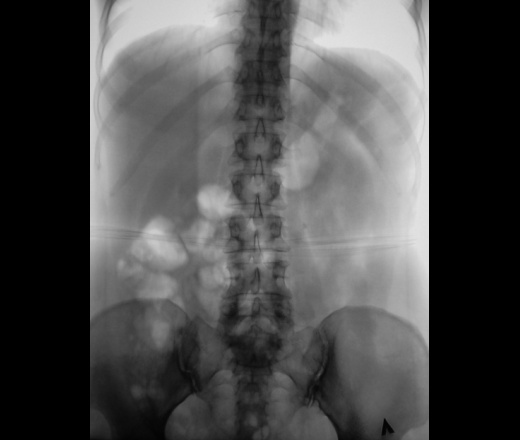

Гидронефротическая трансформация слева вследствие блока, вероятно, частичного, конкрементом в в/3 мочеточника (ПУС).

крррасиво, но сначала запереживал за правую..интересный вариант строения ЧЛС слева, почти неполное удвоение?

Порой, на фоне такой подготовки, сложно разобраться есть оно удвоение, или нет его.